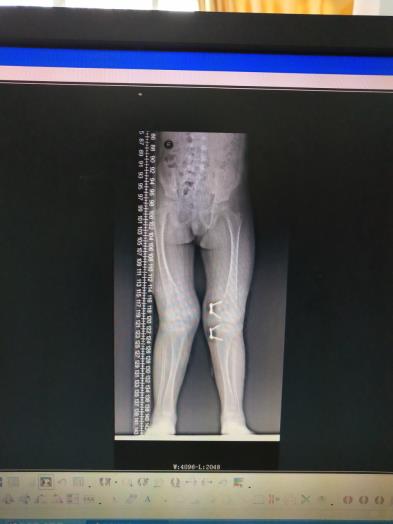

儿童下肢畸形

儿童下肢膝外翻畸形应用“8”字钢板骨骺阻滞术,效果满意